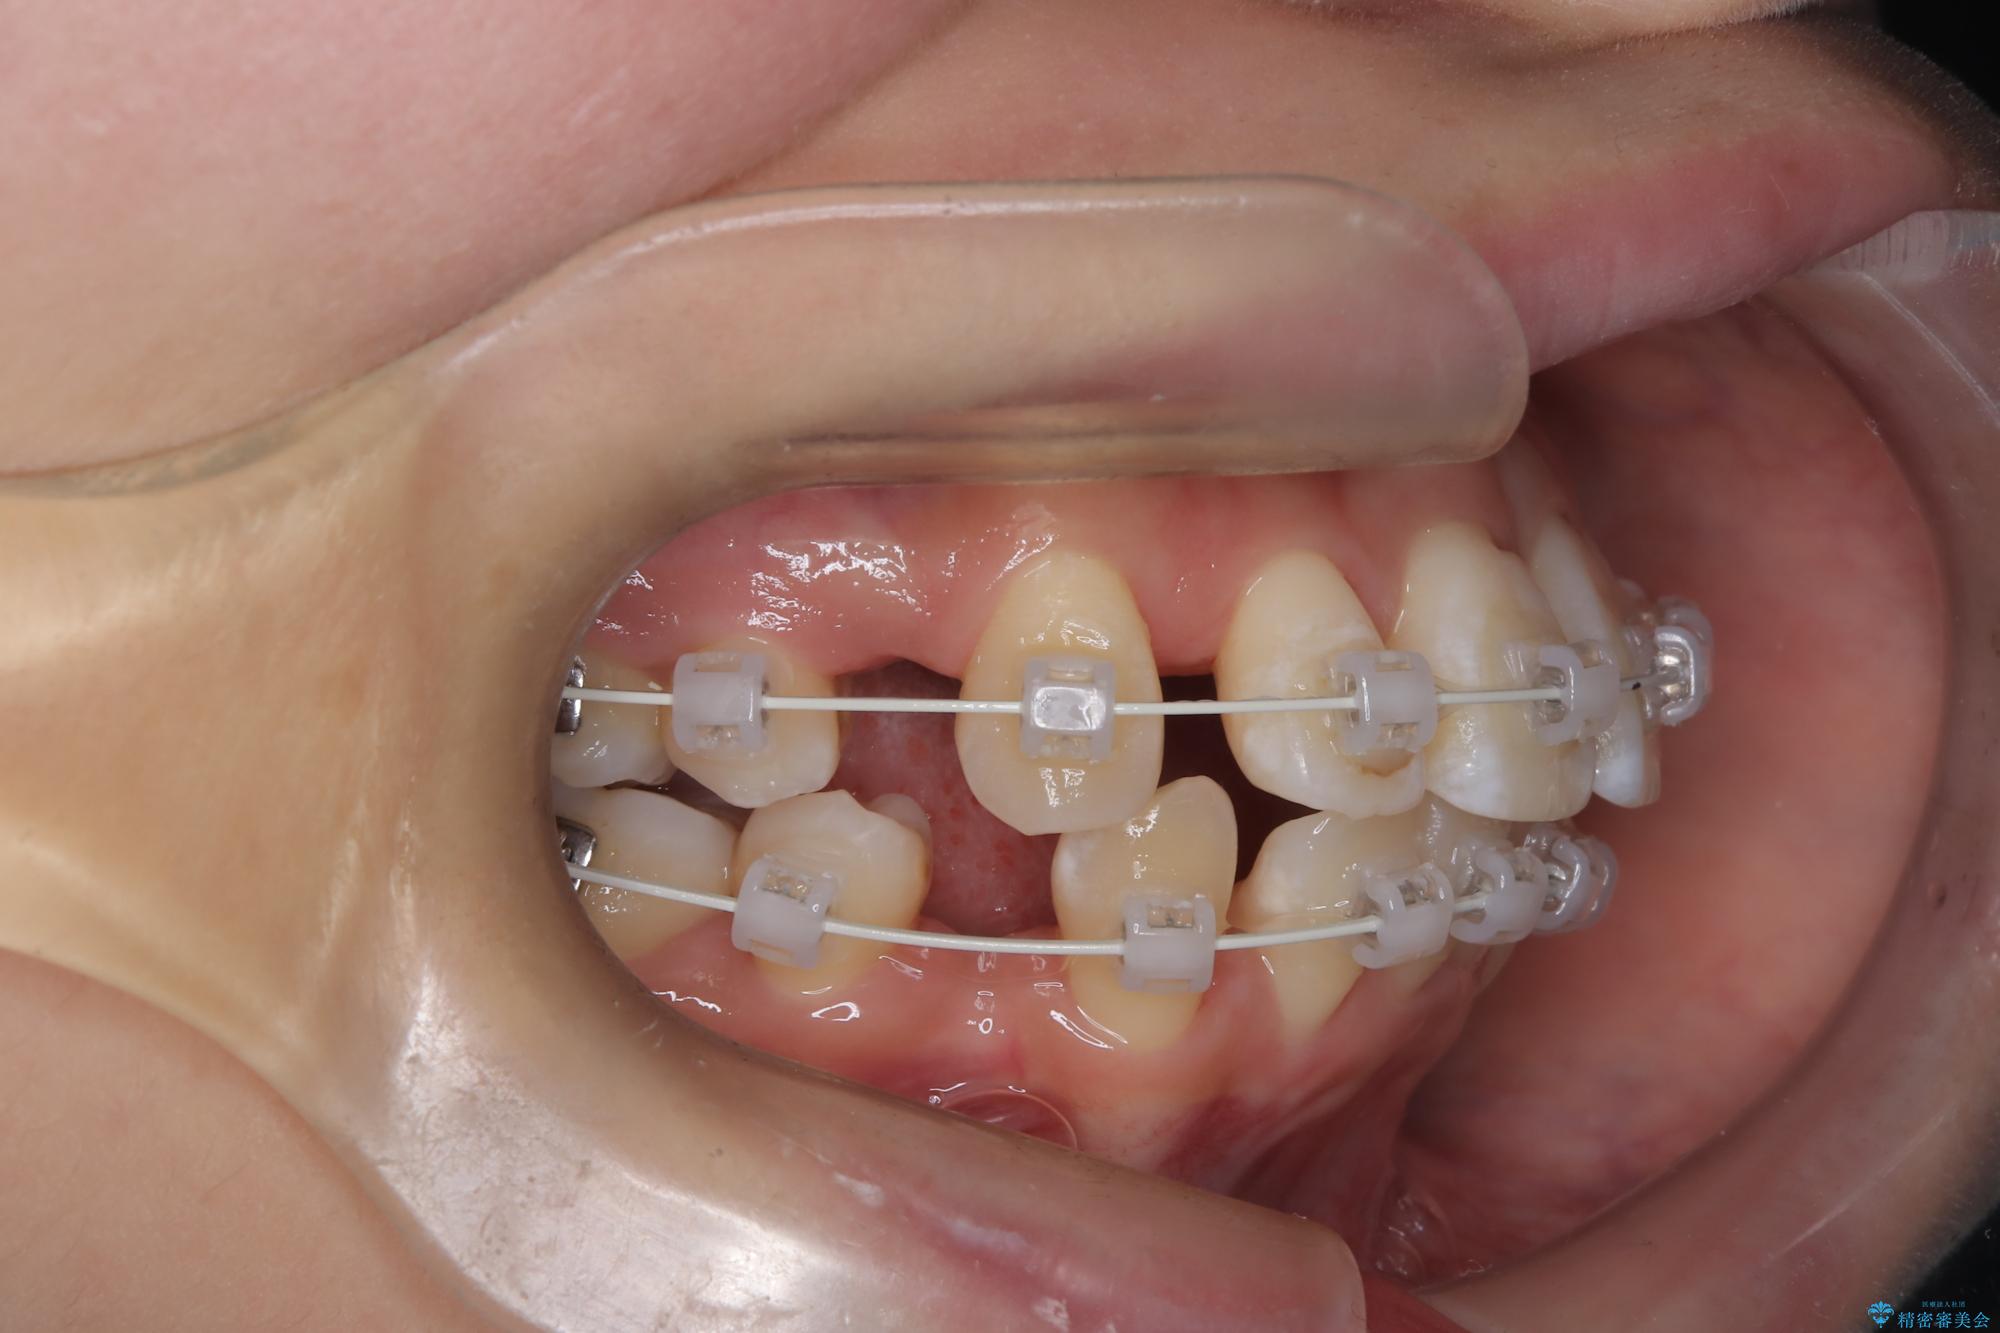

- 八重歯(叢生)と、上下の歯の中心線(正中)がずれていることを主訴にご来院されました。精密な検査の結果、歯列全体のスペースが大幅に不足しており、八重歯を正しい位置に配列し、正中のズレを改善するためには、上下左右の第一小臼歯を抜歯する必要があると診断。装置には、目立ちにくい審美ワイヤーを使用し、見た目を気にせず、機能性と審美性が完璧に整った咬み合わせを目指す治療計画を立案しました。

今回の矯正治療では、まず計画通り上下左右の小臼歯4本を抜歯し、八重歯や正中のズレを解消するための十分なスペースを確保しました。装置には、目立ちにくい白いブラケットとワイヤーを使用した審美ワイヤー矯正を採用。

八重歯: 突出していた八重歯を歯列内に誘導し、デコボコを解消しました。

正中のズレ: 歯を左右対称に移動させることで、上下の歯の中心線を正確に合わせ、顔全体のバランスも改善しました。